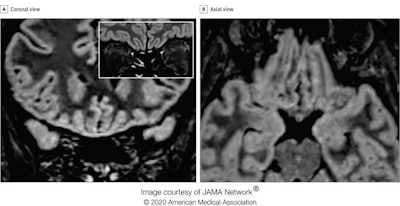

MRI scans of a 25-year-old Italian radiologic technologist who contracted COVID-19 and lost her sense of smell suggest the virus may invade the brain through the olfactory pathway and cause dysfunction of sensorineural origin. This finding was published online by JAMA Neurology on May 29.

"To our knowledge, this is the first report of in vivo human brain involvement in a patient with COVID-19 showing a signal alteration compatible with viral brain invasion in a cortical region (i.e., posterior gyrus rectus) that is associated with olfaction," noted Dr. Letterio Politi and colleagues from the department of neuroradiology at the Scientific Institute for Research, Hospitalization, and Health Care (IRCCS) Humanitas Research Center, Milan. "Alternative diagnoses (e.g., status epilepticus, posterior reversible encephalopathy syndrome-like alterations, other viral infections, and anti-N-methyl-D-aspartate receptor encephalitis) are unlikely given the clinical context."

The researchers performed two MRI exams on a 1.5-tesla scanner using a 20-channel phased-array head/neck coil. They used no contrast agent and acquired 2D and 3D FLAIR, T2-weighted turbo spin-echo, T1-weighted spin-echo, and high-resolution diffusion-weighted images. Constructive interference in steady-state and susceptibility-weighted imaging sequences were also employed.

In follow-up MRI performed 28 days later, the signal alteration in the cortex had completely disappeared and the olfactory bulbs were thinner and slightly less hyperintense. The patient had recovered from anosmia. On May 6, a blood sample was positive for the immunoglobulin G antibodies against the SARS-CoV-2 virus.